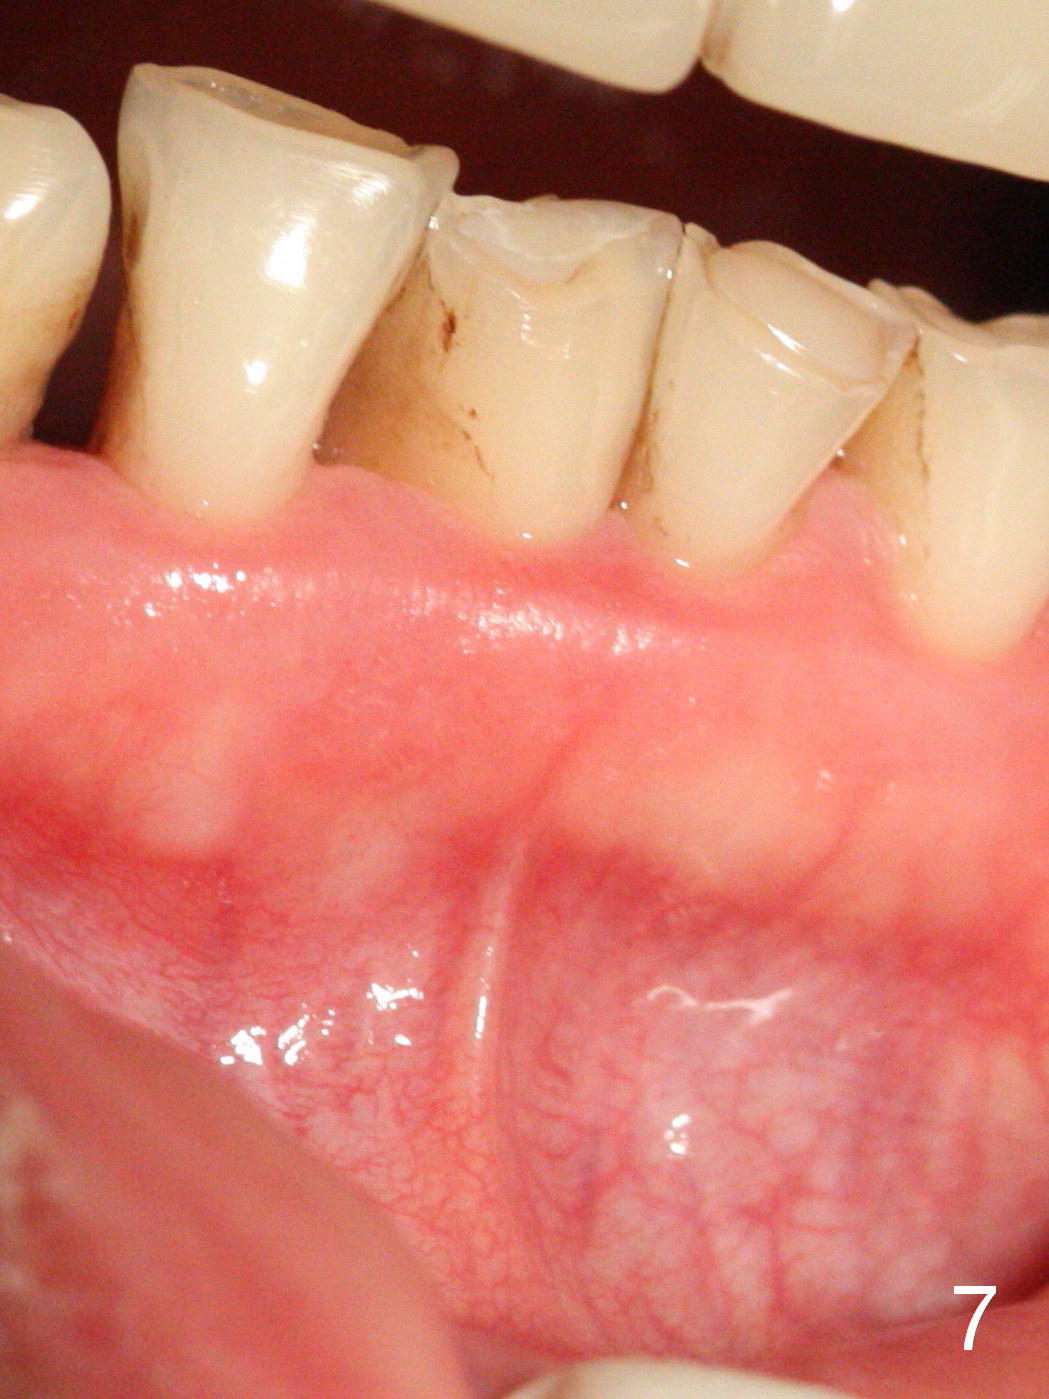

A 45-year-old man has had a chronic fistula associated with the tooth #25 (Fig.1). There is purulent discharge sometimes. After debridement with hand files #10-20 and rotary one 30/06, a master cone 30/.06 is inserted incompletely (Fig.2). After rotary files 30/.08 at 16.0 mm and 30/.10 at 15.0 mm and hand files 10-20 at 17 mm, the master cone is apparently inserted to the WL. With application of Endo Sequence Sealer (syringe), the master cone is reinserted (Fig.3). When the rubber dam is removed, the sealer is found to have expelled from the fistula. With an endo curette (Fig.5), the sealer is removed from the deepest portion of the sinus tract (apex of the tooth). What do you want to know the outcome of the supplementary surgical maneuver? The sealer is gone (Fig.6). The immediately supplementary treatment avoids a separate apicoectomy. No fistula is noted <2 weeks postop (Fig.7). The attrition is due to #8 and 9 veneers, fabricated 8 years earlier. The tooth #24 is symptomatic with loss of incisal composite nearly 4 years postop (Fig.8 <). After 30/.04 gutta percha (GP) try in (Fig.9), RCT is finished without accessory GP (Fig.10).